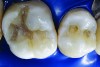

Figure 6. Amalgam is not usually bonded to the walls of the cavity preparation; thus, a space of several microns commonly exists between the restoration and the prepared surfaces. This leads to a potential for microbial invasion and secondary caries, as in this case of these defective amalgam restorations with recurrent decay.

Figure 6